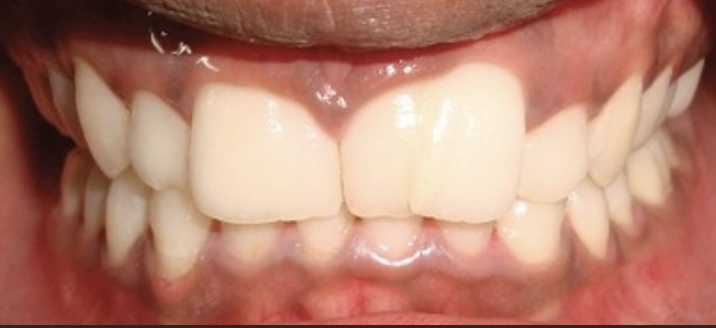

Welke typen amelogenesis imperfecta zijn er?

Hypoplasie en hypocalcificatie.

Wat is hypoplasie?

Hierbij is er een onvolledig ontwikkeld glazuur. Er was dus een stoornis in de vorming.

Wat is hypocalcificatie?

De vorming zelf is normaal maar er is een stoornis in de calcificatie. Er is iets fout gegaan bij de ameloblasten, die dit opbouwen. De vormins is goed maar er mist iets in de mineralisatie.